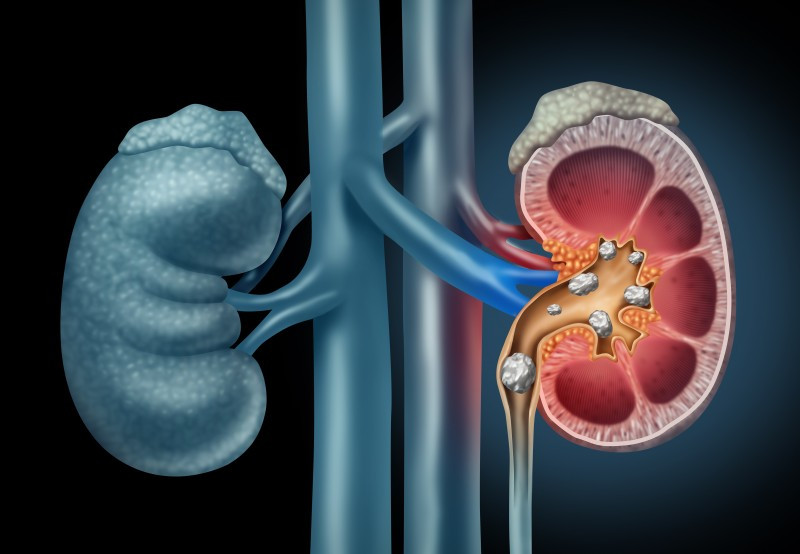

Kidney stones are formations that, once formed, can be disruptive and painful. The formation of kidney stones is largely precipitated by certain dietary and nutrient factors. Here is a look at kidney stones, and some supplements that could help prevent them.

Urine is one of the two primary waste products produced by the body, and it contains a mixture of salts and minerals. The kidneys also control the blood levels of sodium, potassium, calcium, and other minerals. Kidney stones are formations of these minerals. Once formed kidney stones usually present certain symptoms, namely a sharp, cramping pain in the back/side that moves down to the groin, and comes in waves. Frequent, painful urination is also common. Kidney stones are also painful when they pass out of the body since they travel through the urethra. This can be especially painful for men.

Most kidney stones are calcium stones, with most consisting of calcium oxalate, and a minority composed of calcium phosphate. Less than 10% of kidney stones consist of uric acid. Struvite stones are another less common type that occur due to chronic urinary conditions, and cystine stones are a rare type that also come from a certain health condition. These two types are not the focus of this article, however.

Treatments for kidney stones vary. Many stones pass without any complications. A stone less than 5mm in diameter is most likely to pass, while stones between 5-10mm have a roughly 50% chance of passing. Stones that are too large to pass might be addressed by a medication that makes it easier to pass a kidney stone. There are also surgical procedures to break up and help rid kidney stones, which are usually not invasive.